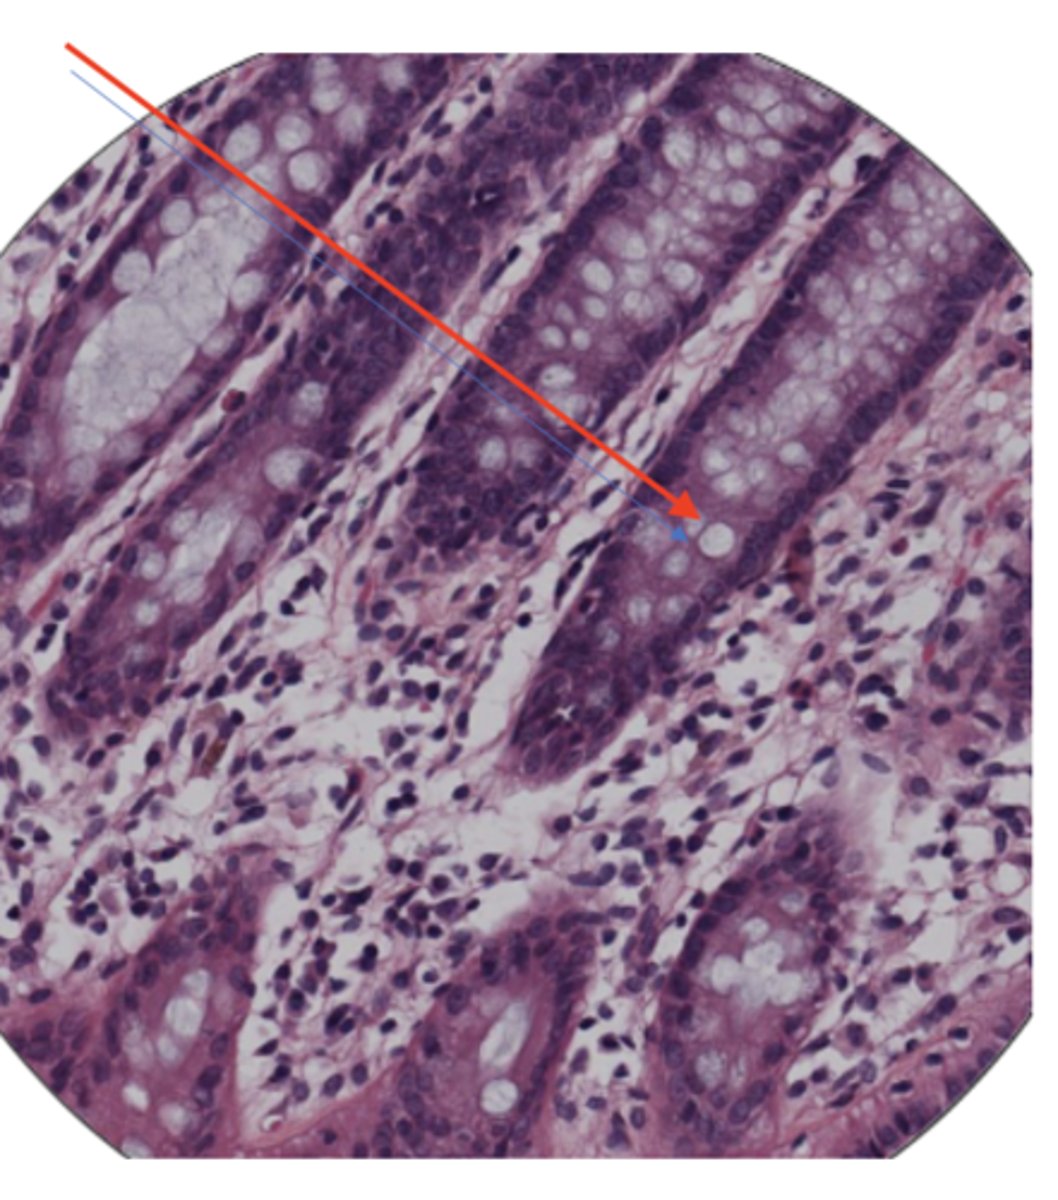

LI submucosa

LI mucosa

LI Muscularis mucosa

LI goblet cells

LI mucosa layer (100)

LI mucosa layer (400)